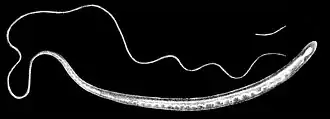

De zweepworm (Trichuris trichiura, synoniemen: Trichocephalus trichiuris, Tricocephalus dispar, Trichocephalus hominis) is een lichtgele tot witte parasiet. De vrouwtjes zijn 35-50 mm en de mannetjes 30-45 mm lang. Het voorste twee derde gedeelte tot en met de slokdarm is smaller dan het derde achterste, dikkere gedeelte, waardoor ze op een zweep lijken.[1] De vrouwtjes hebben een stomp eind en de mannetjes een gekruld eind. De bruine eieren zijn tonvormig en hebben aan de polen uitstulpingen. Ze leven van de uitscheidingen van het slijmvlies, waar ze met de voorkant in vastgeschroefd zitten.

| Mannetje | |||||||||||||

| Vrouwtje | |||||||||||||